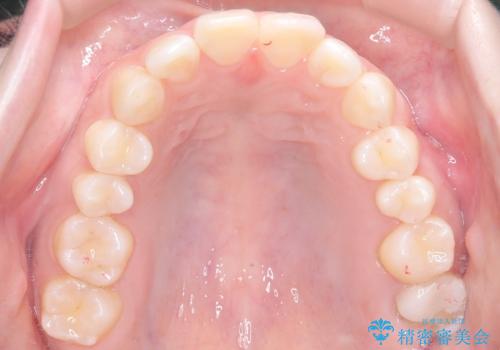

- 前歯のデコボコ(叢生)を気にされてご来院されました。精密な検査の結果、歯が並ぶスペースが不足していることが判明。患者様のご希望から、透明で目立ちにくいインビザライン(マウスピース矯正)による治療計画を立案しました。抜歯を避け、奥歯全体を奥へ動かす遠心移動という方法でスペースを確保し、前歯の叢生を解消することを目指します。

今回の矯正治療では、透明なマウスピース型の装置インビザラインを使用しました。この装置は取り外し可能で、日常生活で目立ちません。治療は、緻密に計算された計画に基づき、段階的に作製されたマウスピースを交換していくことで、奥歯から順に全体を後方へ移動させる遠心移動を実施。これにより、前歯を並べるための十分なスペースが確保され、デコボコが解消されました。抜歯することなく、機能的にも審美的にも整った美しい歯並びを獲得していただけました。